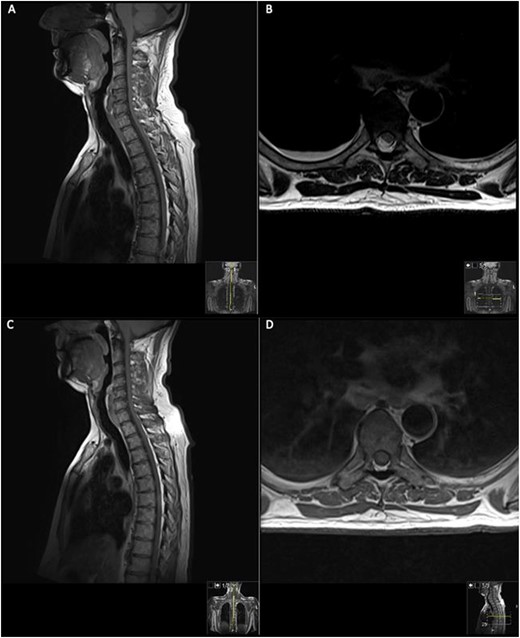

On presentation to A&E, his lower limb power was MRC 4/5 in the right leg and 5/5 in the left leg. Muscle power, sensation and reflexes in the upper limb were intact. He had upgoing plantars and normal lower limb reflexes, except for hyporeflexia in the right ankle reflex. Pinprick sensation was intact until T6 level, however, perianal light touch and pinprick sensation were absent. Urinary function and anal tone remained intact. An magnetic resonance imaging (MRI) spine was requested and discussed by the multidisciplinary team (MDT) (Fig. 1).

MRI on initial presentation; T1 (A) sagittal view sowing mild high signal changes alongside a T2 sequence transverse view (B) which shows the intermediate signal change; when compared with post-contrast T1 sagittal and transverse imaging (C) and (D), showing there is no significant enhancement post-contrast. MRI revealed an intramedullary spinal cord lesion at the level of T6 measuring 24 mm in craniocaudal dimension.